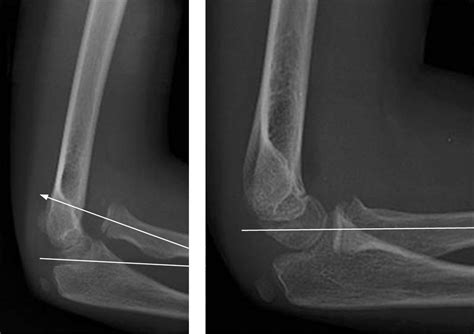

Diagnosing radial head subluxation typically involves a physical examination by a healthcare provider. The diagnosis is usually based on the child's history and the characteristic symptoms. In some cases, an X-ray may be ordered to rule out other potential injuries, such as fractures. However, X-rays are not always necessary for diagnosing radial head subluxation, as the condition is primarily clinical.

• radial head subluxation x ray